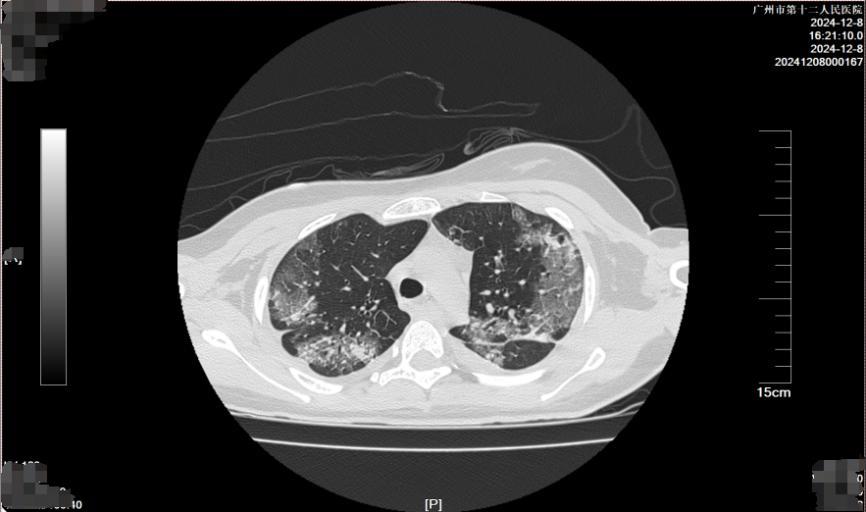

经过4个多小时的转运,到达市十二医院时,小美心率已快到189次/分,血压和血氧饱和度完全测不出。中毒救治中心立即启动绿色通道,从急诊接诊、完成评估检查到收入重症医学科住院,整个过程前后不到20分钟。

血肌酐水平高达760umol/L,转氨酶水平显著升高,提示肾、肝功能严重受损;肌红蛋白水平升高,表明存在横纹肌溶解症;血淀粉酶升高,并发了中毒相关胰腺炎……根据各项检查结果及患者临床表现,重症医学科团队快速敲定了个体化救治方案,其中包括精细化的液体管理、毒物监测指导下的个体化血液净化方案、肺保护下的脑保护措施等,力求在最短时间内稳定患者的生命体征。

2小时后,小美血压、心率等生命迹象逐步稳定,但全身凝血功能障碍、多器官功能衰竭、中毒性脑病等危重状态,仍然提示病情依然不容乐观。张瑞昌表示:“当时患者还出现了凝血功能异常延长,全身多处渗血,不单是皮肤黏膜出血,且口咽和气道出血比较明显,这也给气管插管增加了不少难度。”